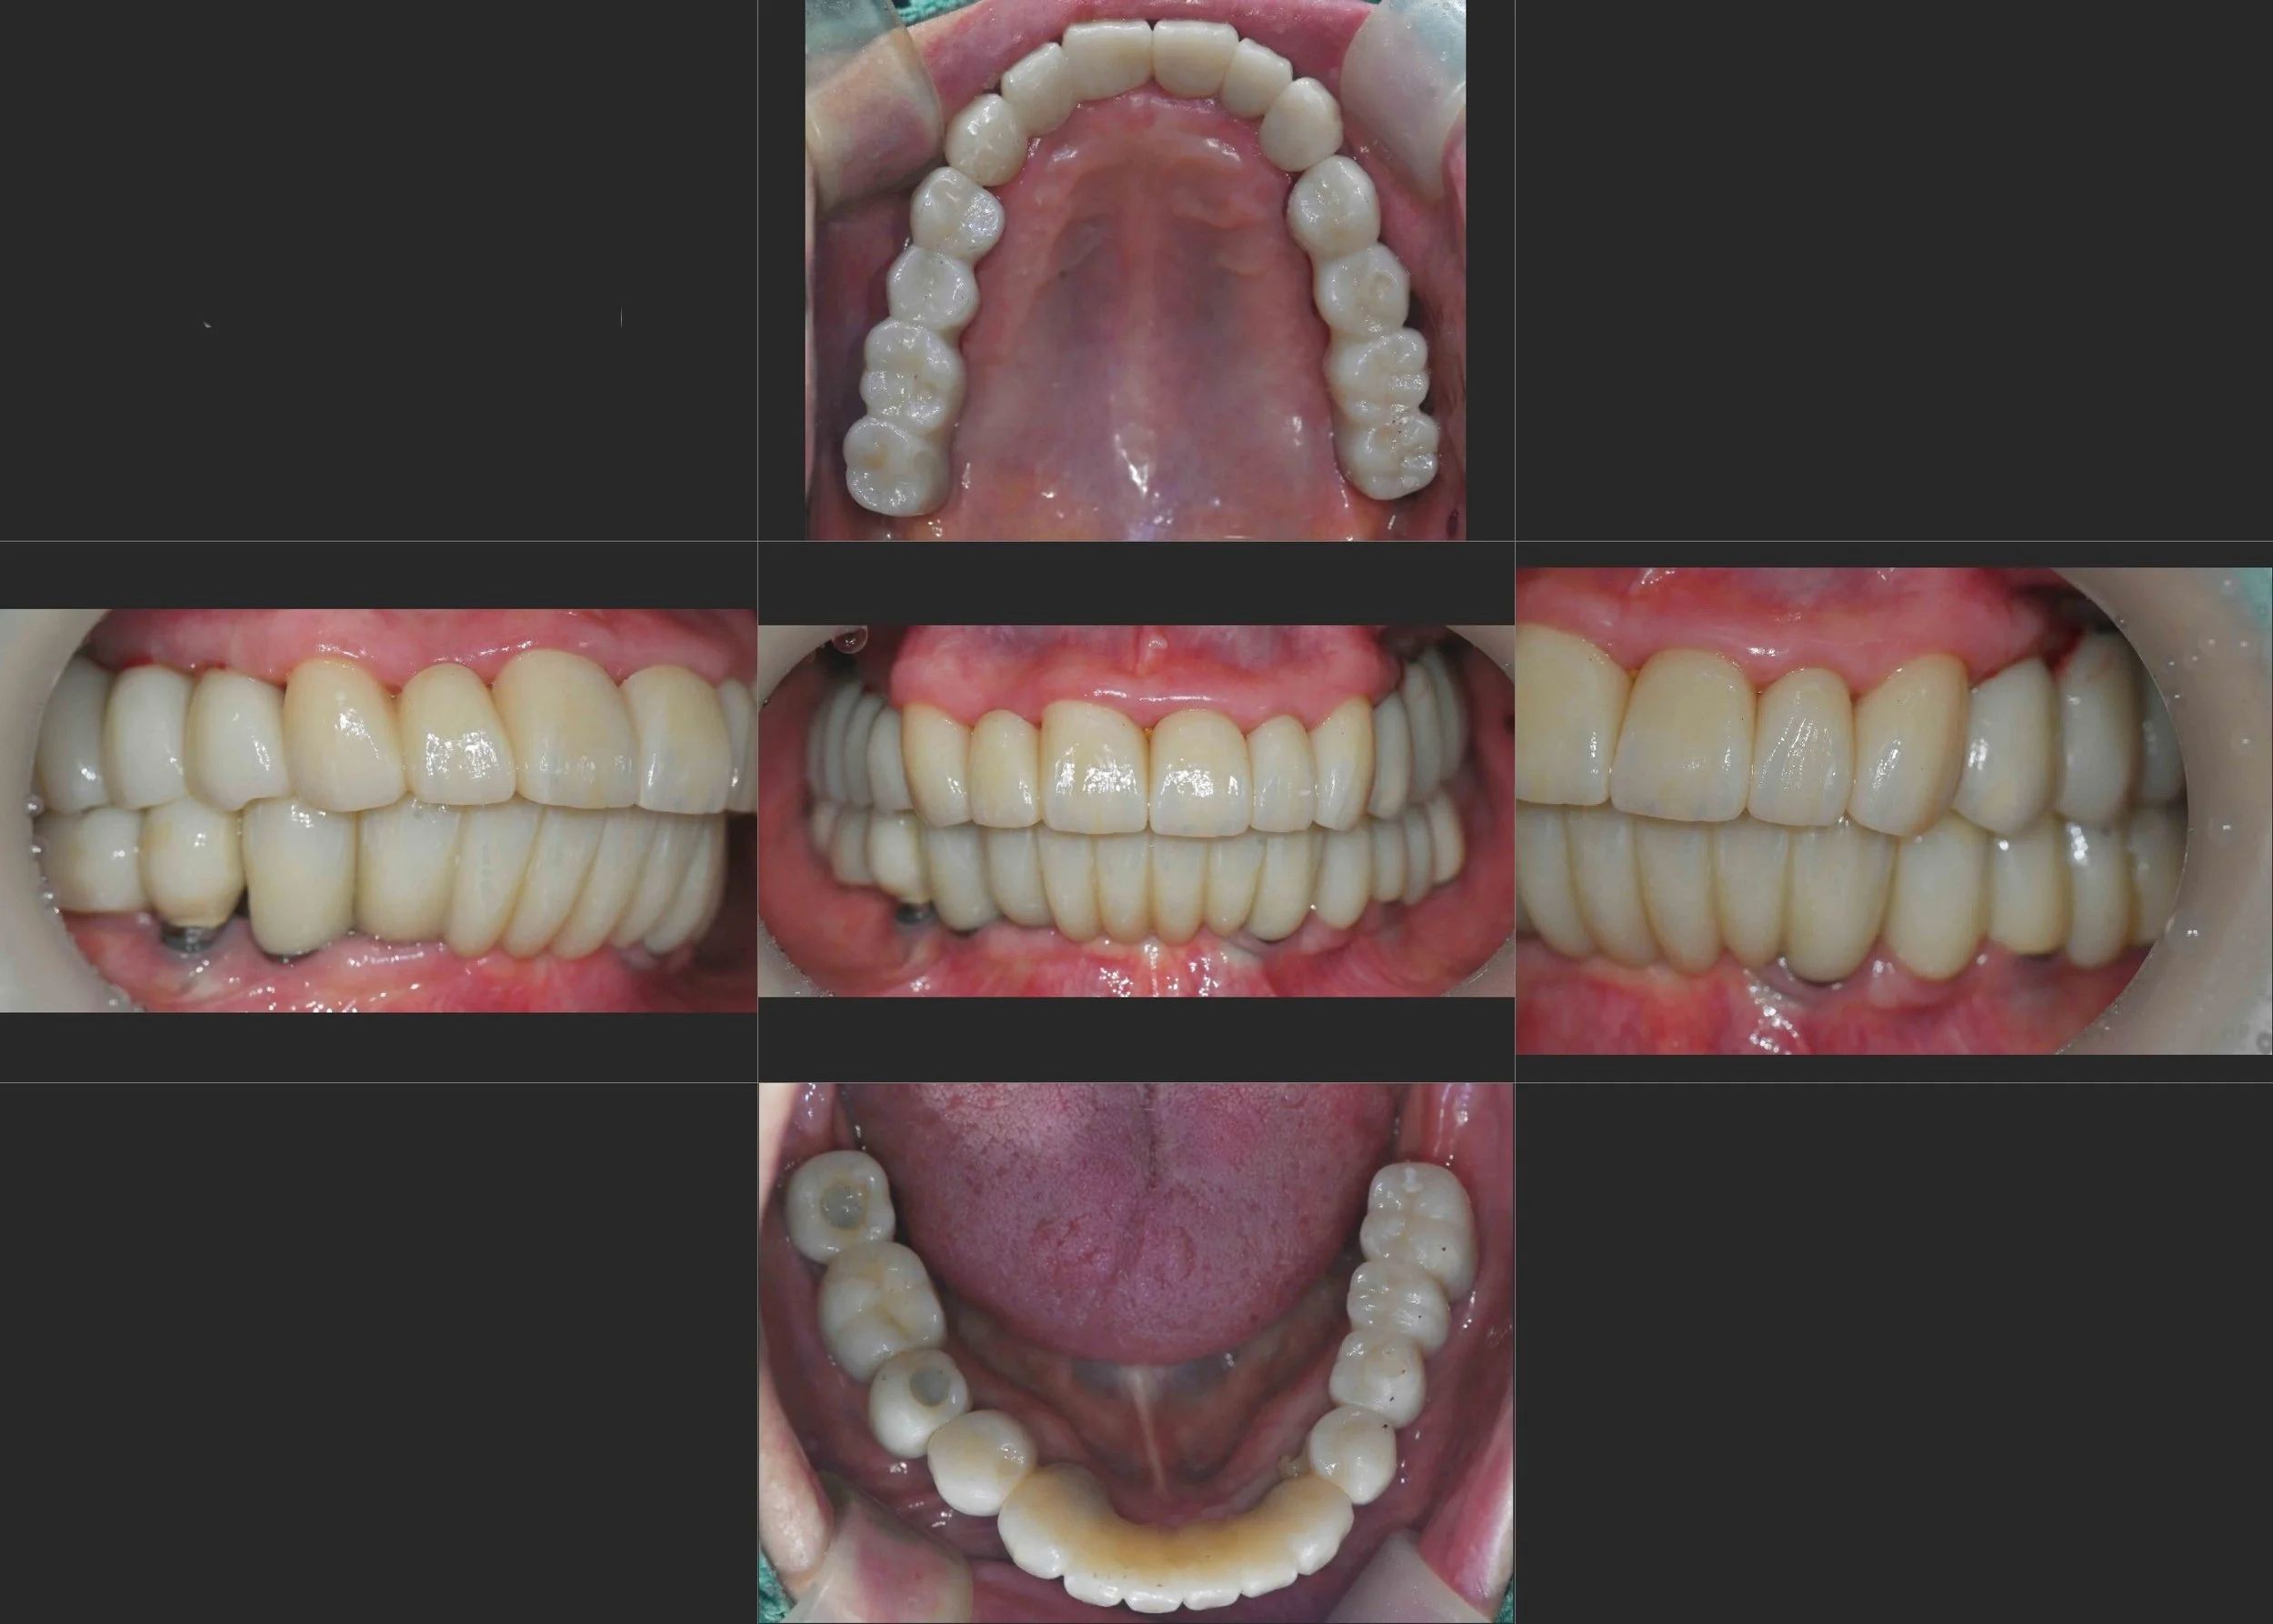

INTRA ORAL - BEFORE

A female patient in her 60s presented with a severely compromised dentition and significant functional distress. Despite having existing implants, a combination of incorrect occlusal design and poor maintenance had led to:

• Gingival and Occlusal Breakdown: The supporting tissues were inflamed, and the overall bite relationship had collapsed.

• Severe Alveolar Bone Resorption: Long-standing disease around poorly-maintained natural teeth had resulted in extreme vertical and horizontal bone loss.

• Functional Failure: The patient suffered from an inability to chew effectively and was dissatisfied with her aging facial appearance caused by the loss of vertical dimension.